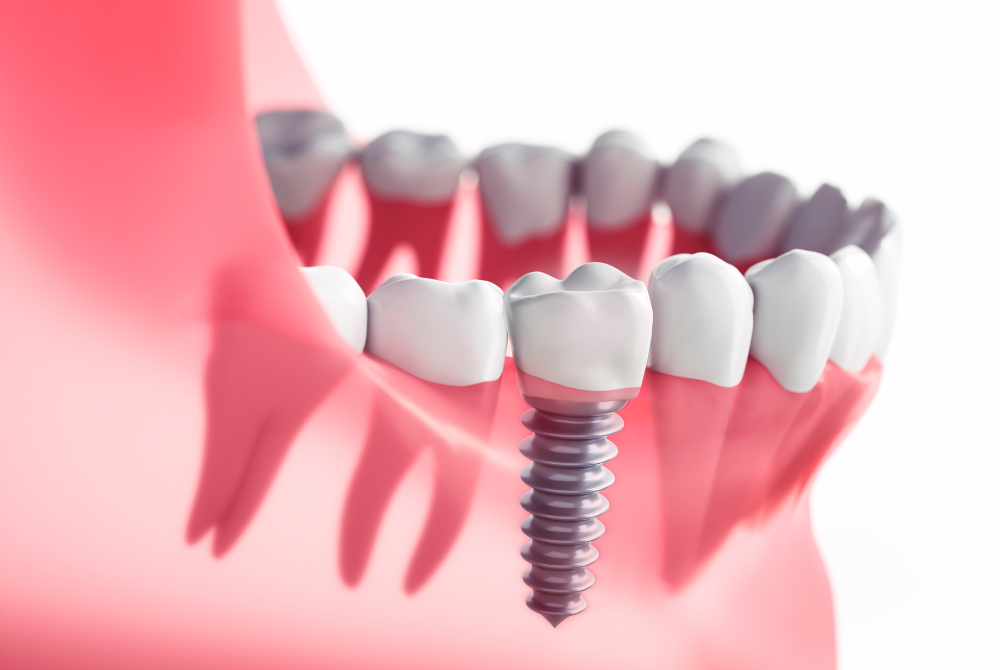

インプラント治療は、失った歯を補うだけでなく、噛む力・見た目・生活の質を取り戻すことができる治療法です。

その点、インプラントは顎の骨に直接固定する治療法です。独立して機能するため、周囲の健康な歯を削る必要がありません。噛む力も天然歯に近く、硬いものも安心して食べられるようになります。さらに、見た目も自然で、周囲の歯と調和した仕上がりが期待できます。